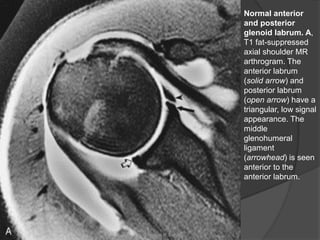

Normal anterior

and posterior

glenoid labrum. A,

T1 fat-suppressed

axial shoulder MR

arthrogram. The

anterior labrum

(solid arrow) and

posterior labrum

(open arrow) have a

triangular, low signal

appearance. The

middle

glenohumeral

ligament

(arrowhead) is seen

anterior to the

anterior labrum.